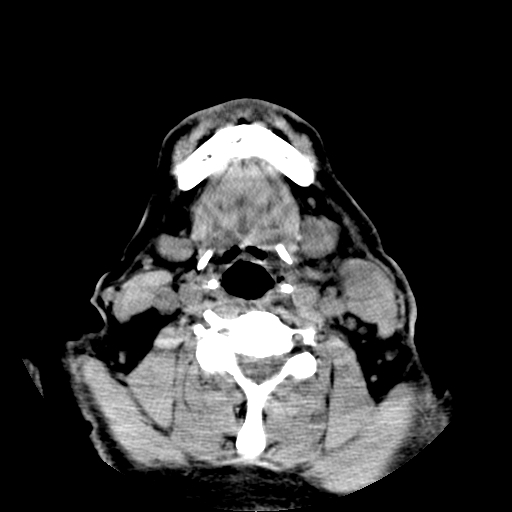

以下是引用卜一在2007-8-6 21:23:00的发言:[br]定位:左侧胸锁乳突肌内侧 颌下腺下后方。特征:弥漫性生长 软组织密度肿块,界限不清,内隐约见低密度坏死。考虑:神经源性肿瘤或血管源性肿瘤。

以下是引用wangzhanshuang在2007-8-6 21:08:00的发言:[br]腮腺混合瘤